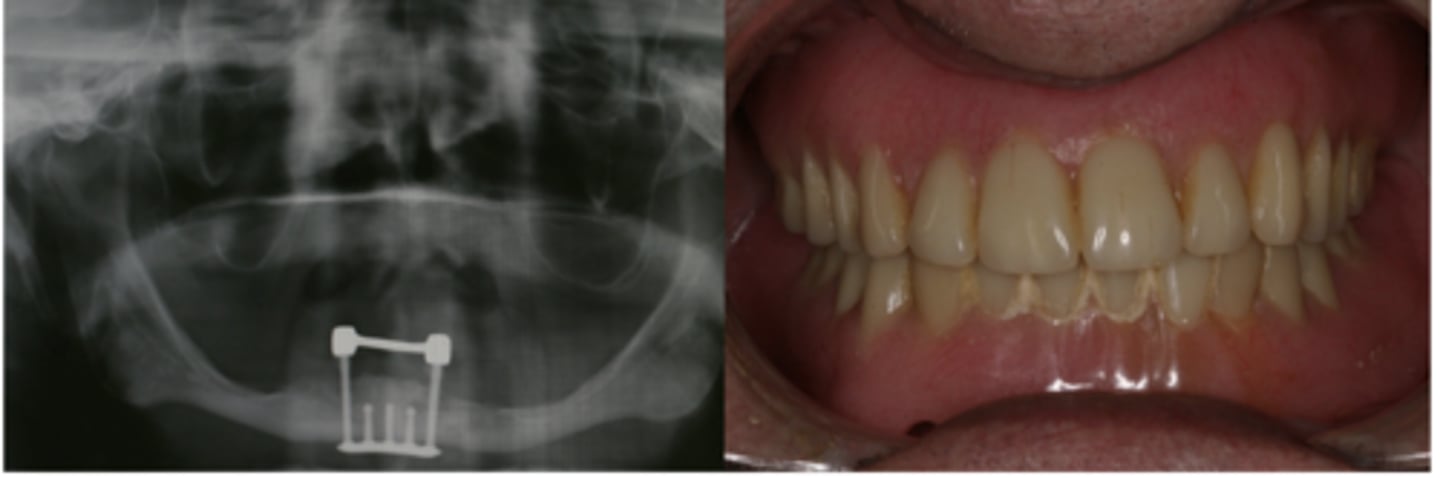

Implant-retained/ tissue-supported

Describe the retention and support for this denture

Implant-retained/ implant- supported